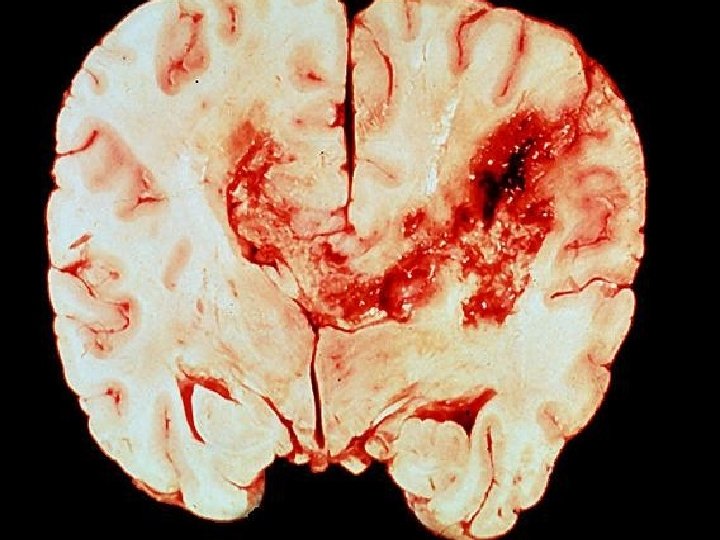

Litbrigði MTK � Hvíta efnið: Skapast af mýelíni, sem er fituefni og notað er til að einangra taugasíma sem eru að bera boð langar leiðir � Gráa efnið: Bendir til mikils fjölda frumubola og tengsla milli fruma